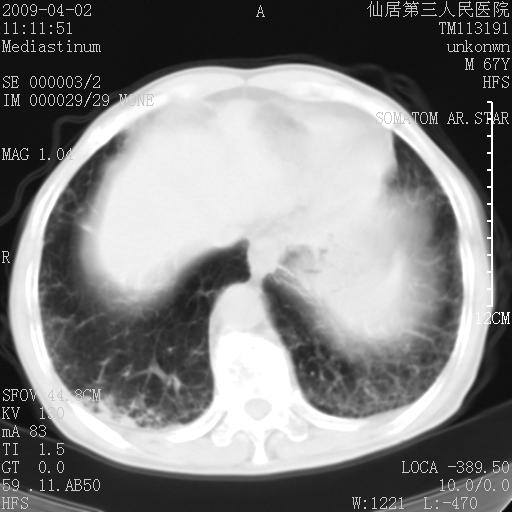

患者老年男性,乏力畏寒来诊,摄胸片示右下肺感染性病变,抗炎两周后复查胸片,无好转有进展。

后做ct平扫表现如下:

考虑右肺炎症可能性大,不除外细支气管肺泡癌

是否还要考虑肺间质纤维化,建议hrct扫描。

考虑间质性肺炎。

病灶呈蜂窝征,纵隔多个淋巴结肿大;肺泡癌需考虑

右肺下叶背段干酪性肺炎。请痰检[emb28]

考虑双肺间质性改变(间质纤维化?)伴右肺下叶感染。